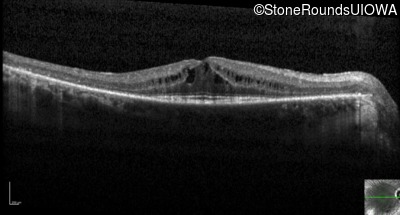

Optical Coherence Tomography - Right - 20/40 +2

Exemplar / OCT Stack

OCT Stack